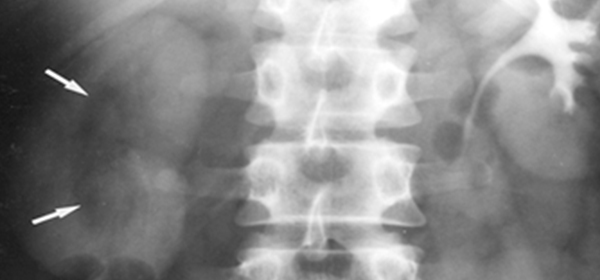

½ÅÀå¿ä°ü¹æ±¤´Ü¼øÃÔ¿µ(KUB)